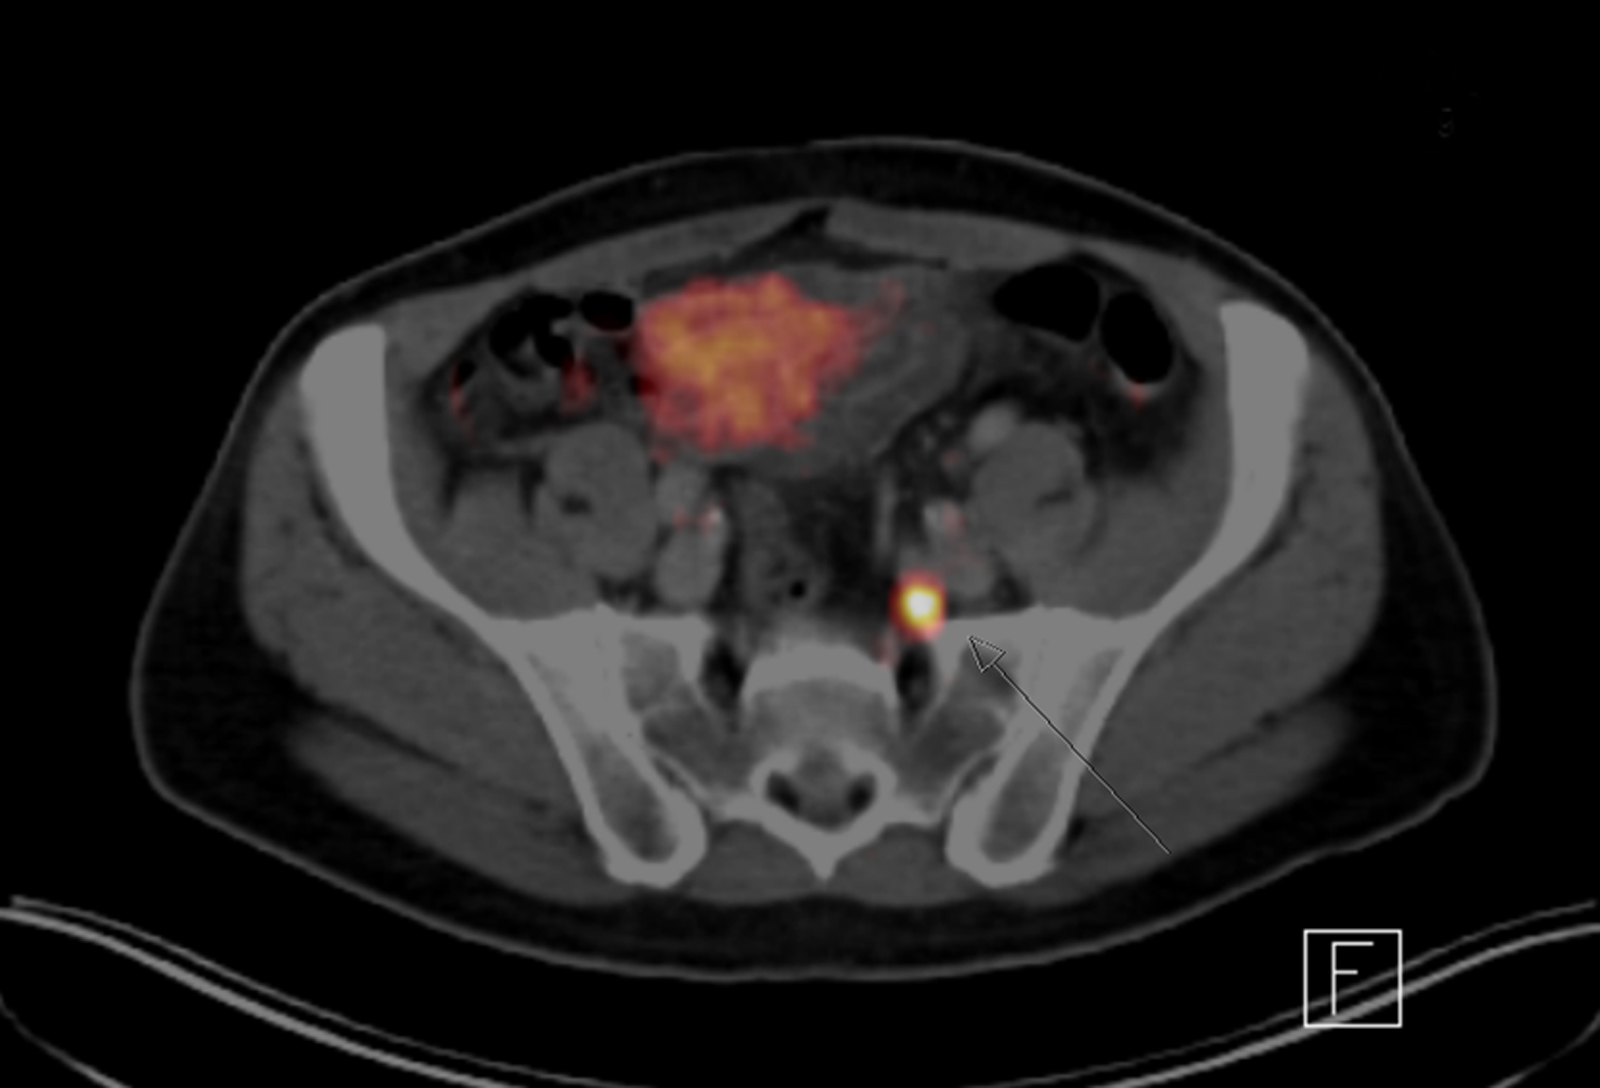

Durch an der TUM entwickelten Radioliganden können auch sehr kleine Metastasen sichtbar gemacht werden. Auf dieser PET/CT-Aufnahme ist ein veränderter Lymphknoten zu erkennen (Pfeil). (Foto: Nuklearmedizin / TUM)

Mithilfe einer Positronen-Emissions-Tomografie (PET) die mit einer CT oder MRT kombiniert wird,  lassen sich die die nun Strahlung aussendenden Metastasen sichtbar machen und zeitgleich die genaue Lage der markierten Zellen bestimmen. Bei der Entwicklung und Anwendung des Verfahrens arbeiten Radiochemiker, Nuklearmediziner und Urologen der TUM eng zusammen. Anhand der gewonnenen Daten können die Ärzte erkennen, ob eine Operation sinnvoll wäre und gemeinsam mit dem Patienten  die Entscheidung für oder gegen einen Eingriff treffen. Neben den Ergebnissen der PET/CT-Untersuchung fließen aber auch Faktoren wie die physische Verfassung des Patienten in die Empfehlung der Mediziner ein.